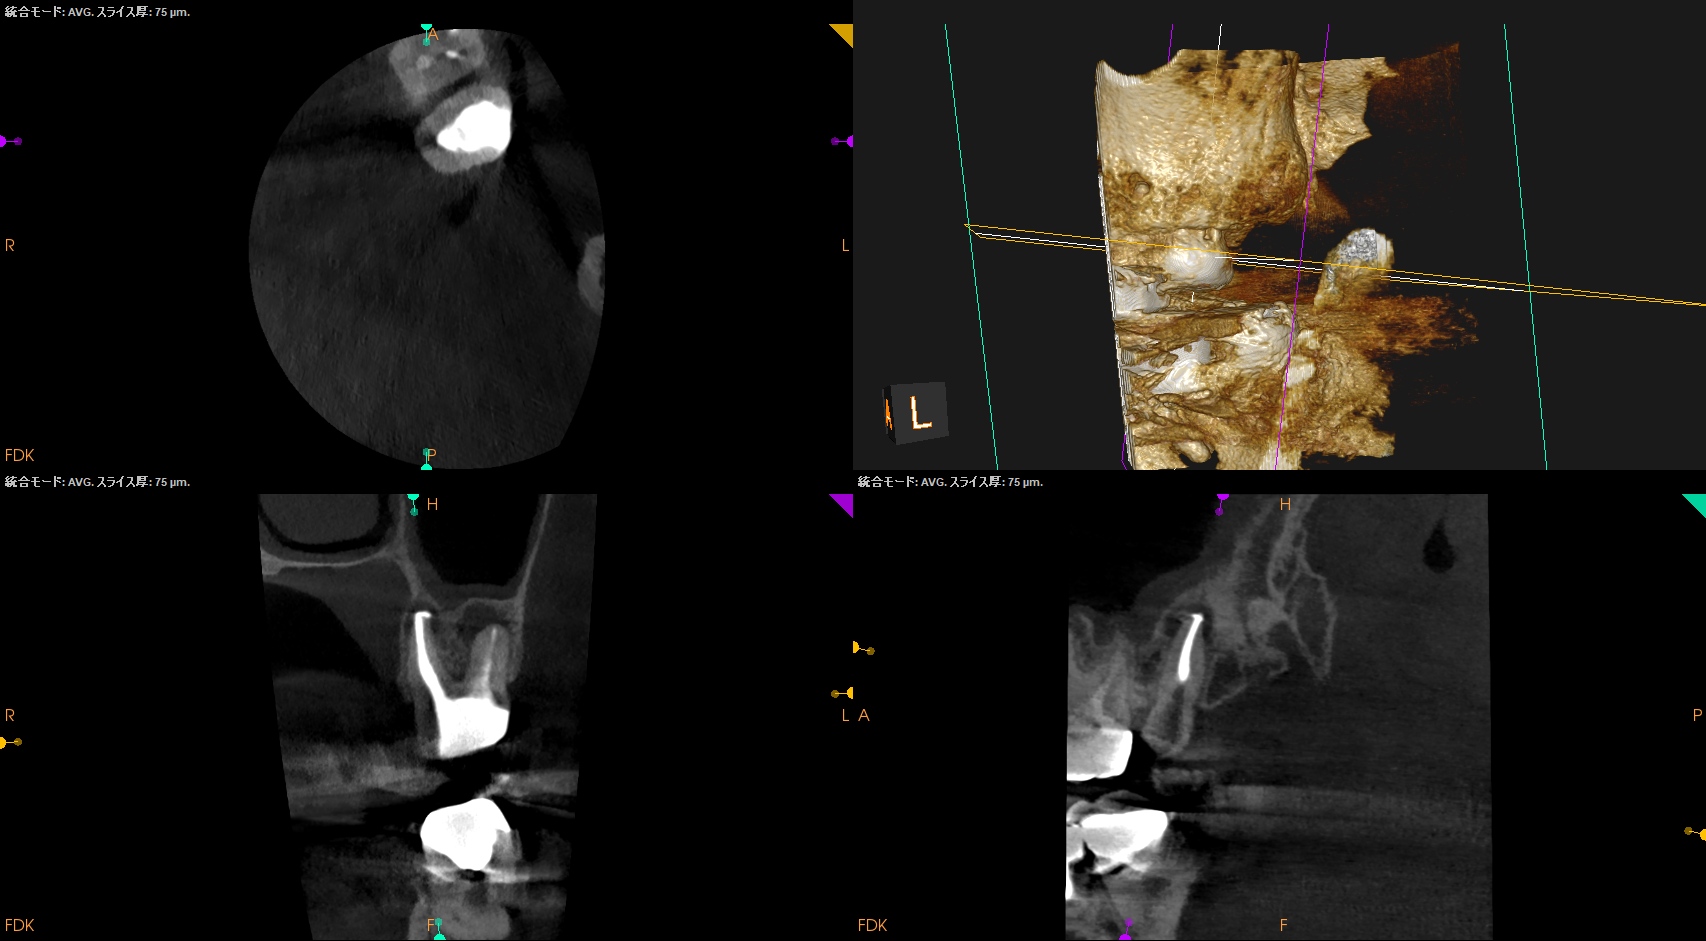

術後のPA, CBCTは以下である。

MB1

MB2

DB

P

問題はないだろう。